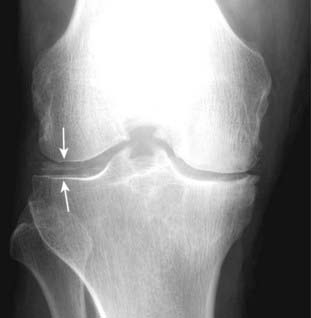

Figure 23-11 Chondrocalcinosis.

Chondrocalcinosis refers only to calcification of the articular cartilage (solid white arrows) or fibrocartilage and is seen in about 50% of adults over the age of 85, most of whom are asymptomatic. If this patient had acute pain, redness, swelling, and limitation of motion, the combination would be called pseudogout.